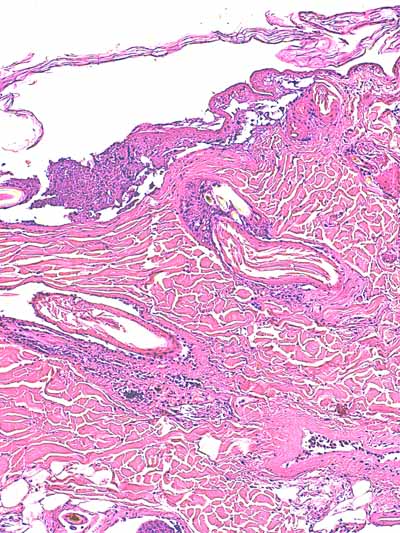

Photo 2 (Hémalun Eosine X 40) : biopsie réalisée en marge d’un ulcère.

L’épiderme, fragilisé, se détache artéfactuellement et se désolidarise du derme superficiel.

Le derme montre une plage cellulaire dense qui s’étend du derme superficiel jusqu’au derme profond.

En contact avec cette plage, se trouve un follicule pileux dont la tige pilaire est fragmentée

et circonvolutée dans son fourreau épithélial.

Légendes de la Photo 2 :

- Pointe de flèche orange : ulcère

- Ovale jaune : plage cellulaire inflammatoire s’étendant du derme superficiel au derme profond

- Flèche turquoise : follicule pileux dont la tige pilaire est fragmentée et circonvolutée dans son fourreau épithélial

- Flèches jaunes : épiderme fragilisé qui se détache du derme

- Double flèche orange : épaisseur épidermique

- Double flèche verte : épaisseur dermique

- Double flèche bleue : épaisseur hypodermique